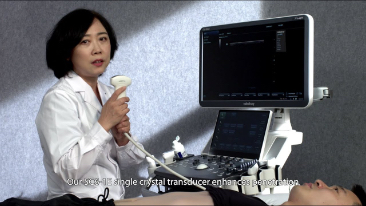

Sistema de diagnĂłstico ecogrĂĄfico

DC-80A

Transductores